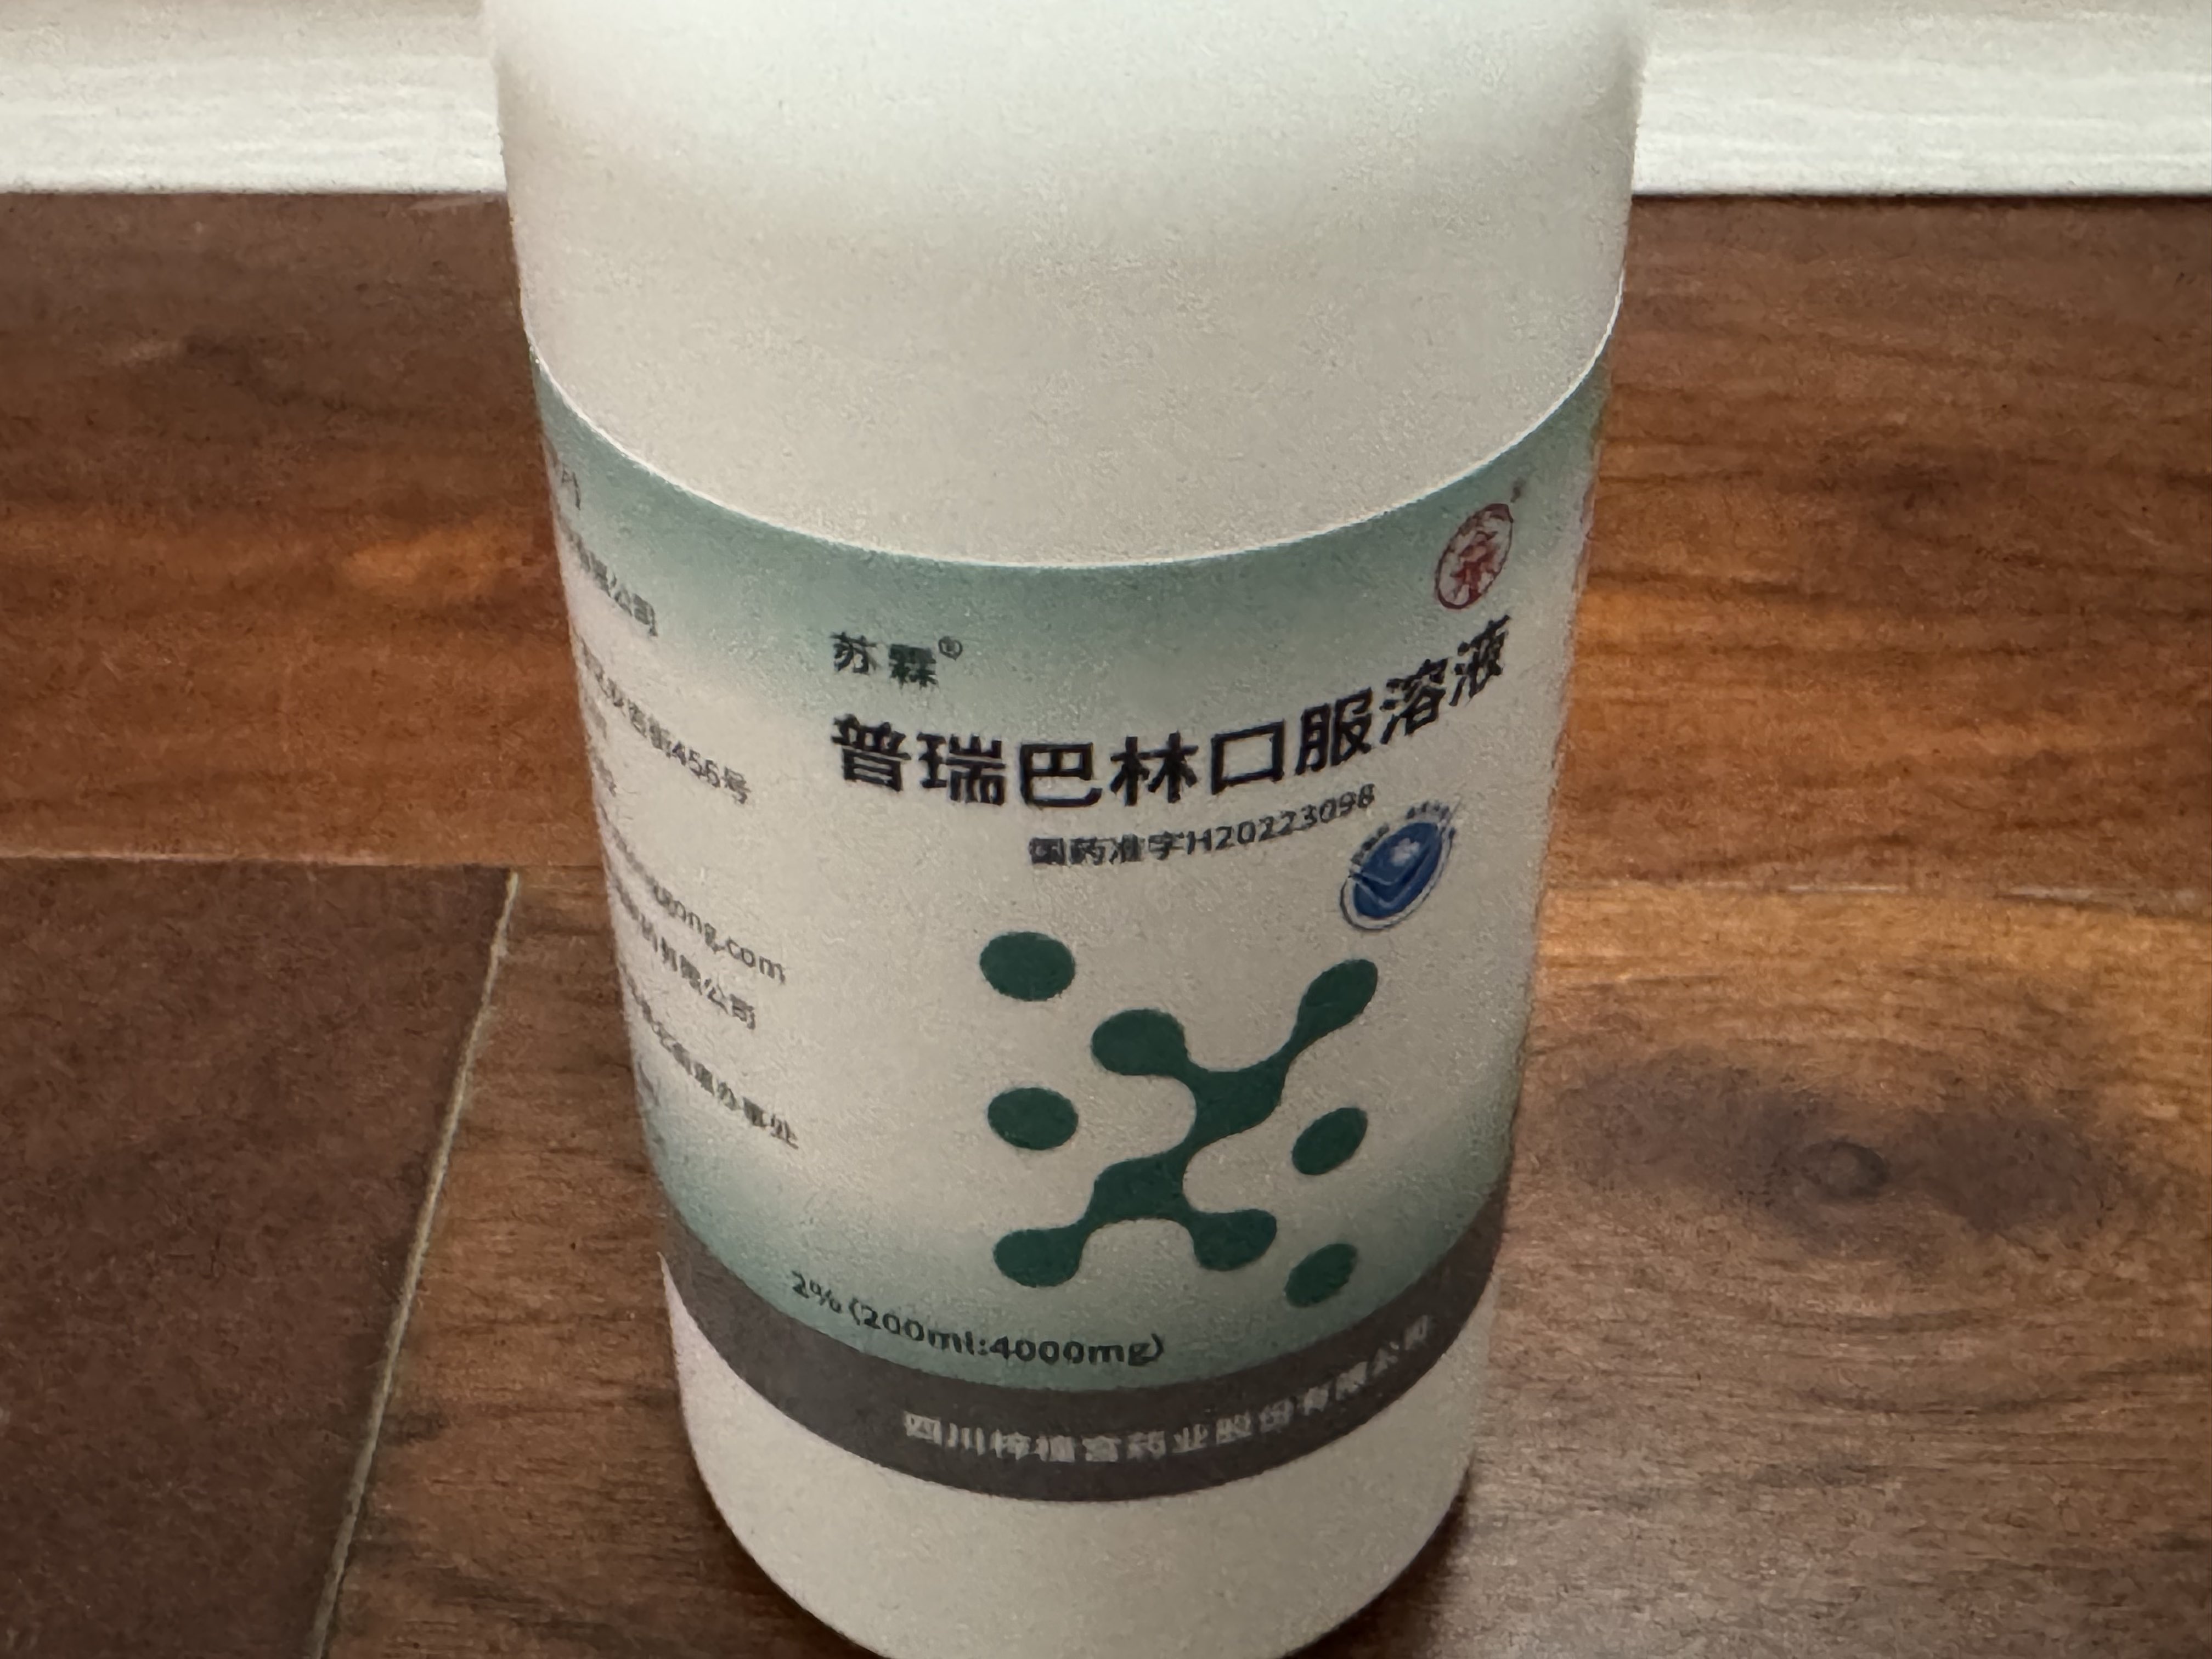

2024-08-14 11:34:53 UTC

甚至在第二天有余晖的感觉,虽然发生了很多破事但没怎么影响心情*抗焦虑&镇静

运动协调性稍差,表现为走路和站立时平衡不好

此剂量下对睡眠的改善作用,增加了慢波睡眠且没有影响rem,精力恢复+

FDA数据,在临床剂量下(75-600mg)普瑞巴林的依赖性低于bzd,并相比之下它产生的认知和精神运动障碍较轻 https://t.co/TJ7ZOQ7pbC